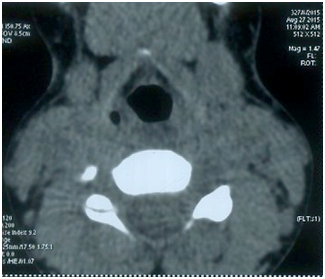

A 10-year-old male child presented to our department with history of midline neck swelling present for one year. There was no history of compressive symptoms such as dysphagia, dyspnea, dysphonia, recurrent respiratory tract infections and neither there was history suggestive of hypothyroidism or thyrotoxicosis. General physical examination appeared to be normal. A midline non-tender neck swelling of size 2.5x1.5 cm was present in sub hyoid region with smooth margins and firm consistency Figure1. Swelling was moving with swallowing and protrusion of tongue. Clinical diagnosis of Thyroglossal cyst was made. Haematological investigations were as follows; Hb-11gm%, Bleeding time-2’10 sec, Clotting time- 4’20”, TLC 8,000/cmm. Urine examination was normal. TSH was 6.0 mU/ml while T3 and T4 were 1.2 and 42 nmol/l respectively. Ultrasound neck showed a heteroechoic lesion of size 2.3x1.5 cm in sub hyoid region with flow on colour Doppler and was moving with deglutition and no normal thyroid gland at usual location. Fine niddle aspiration cytology was done showing features suggestive of hyperplasic change in Thyroglossal cyst or colloid cyst. Computed tomography was done which confirmed findings of ultrasound Figure 2. Patient was started on thyroxin. Radioisotope scan was not done due to age of patient. Patient has done well in follow up with normal thyroid profile.

Figure 2 Fine niddle aspiration cytology was done showing features suggestive of hyperplasic change in Thyroglossal cyst or colloid cyst. Computed tomography was done which confirmed findings of ultrasound.